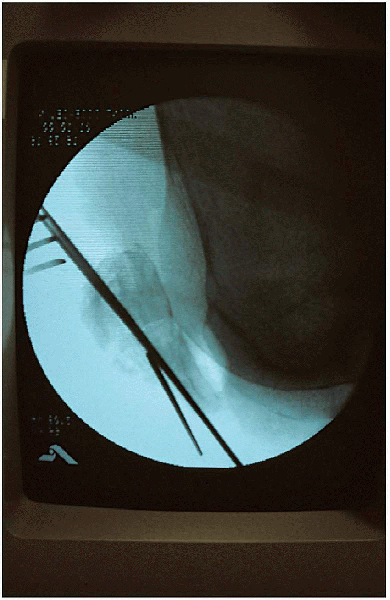

![]() |

FIGURE 29-12.

Lateral radiograph verifying fracture reduction and implant position. An additional Kirschner wire had been placed in the distal fragment because of a nondisplaced, longitudinal fracture fragment. |